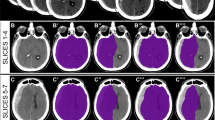

CT images were obtained on a SOMATOM CT system (Siemens, Germany). All CT images were non-contrast-enhanced 5-mm axial sections obtained parallel to the orbitomeatal baseline at 135 kV and 150 mA. Images were viewed on a 512 × 512-pixel monitor on an electrical communication system. We obtained standardized HU measurements of the WM and GM at 6 points: the injury and non-injury site at each of the frontal, temporal, and occipital lobes, while avoiding the site of brain hemorrhage. Two radiologists standardized the placement of the measurements at the basal ganglia level.

The radiologist drew a centerline from the frontal pole to the occipital pole and placed hallmarks at the quarter, halfway, and three-quarter points to divide the centerline length into 4 equal parts. The radiologist then drew lines perpendicular to the centerline to the right and left of these three hallmarks and placed regions of interest (ROIs) (10 mm [2]) along these lines at 10 mm inside the cranial bone or hematoma on either side as three measurement points of the GM and at 15 mm inside of these points as three measurement points of the WM (Fig. 1). The HU values of the WM or GM were calculated as the mean HU value of the WM and mean HU value of the GM. We also measured the displaced distance from the median (DDM), which is the difference between the centerline of the line and the centerline of the anatomical mark (Fig. 1). We assessed the correlation between outcome and HU measurements of the WM and GM or DDM.

Inter-rater reliability of the two radiologists is presented in Table 2. The kappa value (k = 0.80–0.87) indicates substantial to almost perfect inter-rater reliability. The HU values of the injury or non-injury site are indicated in Figs. 2 and 3. Only the HU value of WM in the injury site of the death group was decreased significantly. There was no significant difference in the DDM between the survival group and death group (p = 0.25) (Fig. 4). We also reanalyzed the DDM-derived hematoma thickness. The hematoma thickness was 5.2 ± 1.2 mm in the death group and 3.8 ± 2.0 mm in the survival group. There was no significant difference in the DDM subtracted hematoma thickness between the survival group and death group (p = 0.45). However, the DDM in the death group was slightly higher than that in the survival group. The DDM did not correlate with the initial FDP, SBP, or GCS. ROC analysis for HU of WM of the injury site is shown in Fig. 5. A cut-off value of 31.5 for HU of WM showed 80.0 % sensitivity and 99.9 % specificity for death; the AUC was 0.91. Of the 24 surviving patients, however, only two had a HU value of less than 31.5.